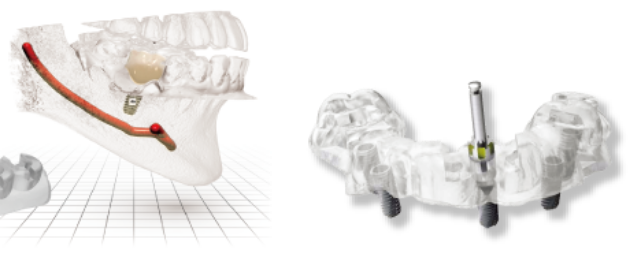

都歯デンタルクリニックではOSSTEM社の「One Guide System」を導入しています。

治療前にデジタルシミュレーションを通し、患者様ひとりひとりに合わせたOneGuideと呼ばれるガイドテンプレートを製作し、手術時にそれを装着することで、歯茎を切開せずともズレがなく、正確な位置に埋入するインプラント治療が可能です。

- 1診断CTを利用し3D診断を行います

- CT撮影した3Dデータを通し、顎の骨、歯肉、神経を総合的に考慮し、精密な診断をします。

- 2計画専用のソフトウェアで

手術計画を立案 - デジタルシミュレーションを使用し、インプラント手術位置を設定し、そのまま手術ができるようにひとりひとりの患者様に合ったOneGuideを製作します。

- 3手術OneGuideを装着し、手術します

- 完成したOneGuideを手術前に口腔内に装着し計画通りの位置で安全かつ正確に手術します。

痛みを減らし、回復は早く

歯肉を切開せずにインプラントが入る程度の小さなホールを開けて手術します。